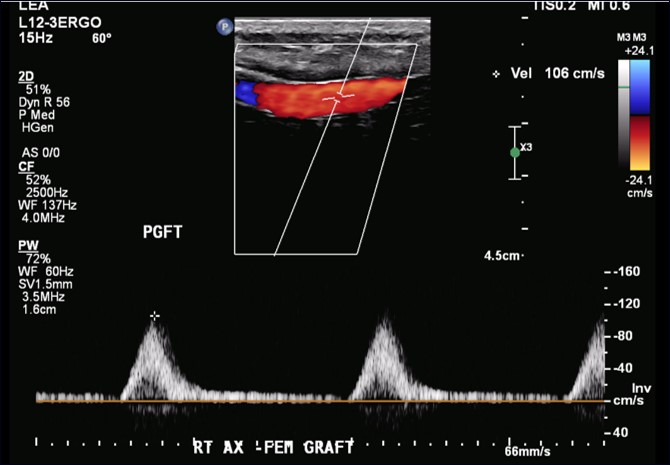

The Artix device time was 25 minutes. The patient tolerated the procedure well without complications and was discharged 2 days later. Follow up 1-month arterial duplex demonstrated graft patency, and the patient had no new symptoms of limb ischemia (Figure 5).